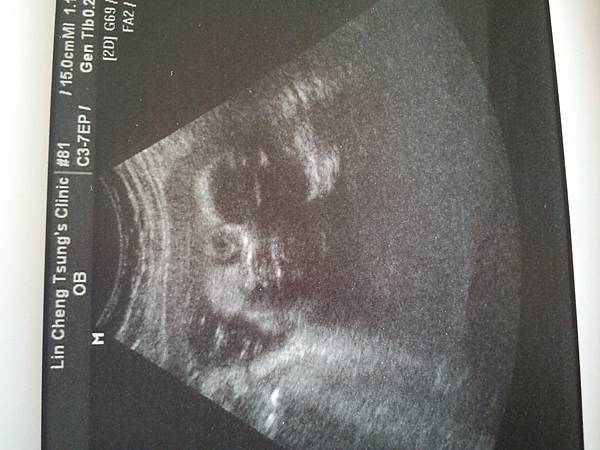

距離上次產檢才隔兩週,我的體重才增加0.4公斤

而捲捲呢,也是增加了400g,到了1675g。

頭圍是大兩週,因為是要自然產,所以醫生說 可以不用吃DHA了。